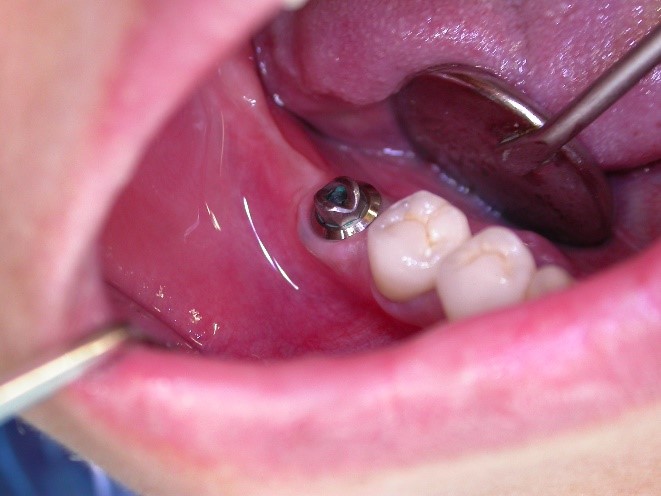

Implantát v postranním úseku chrupu.